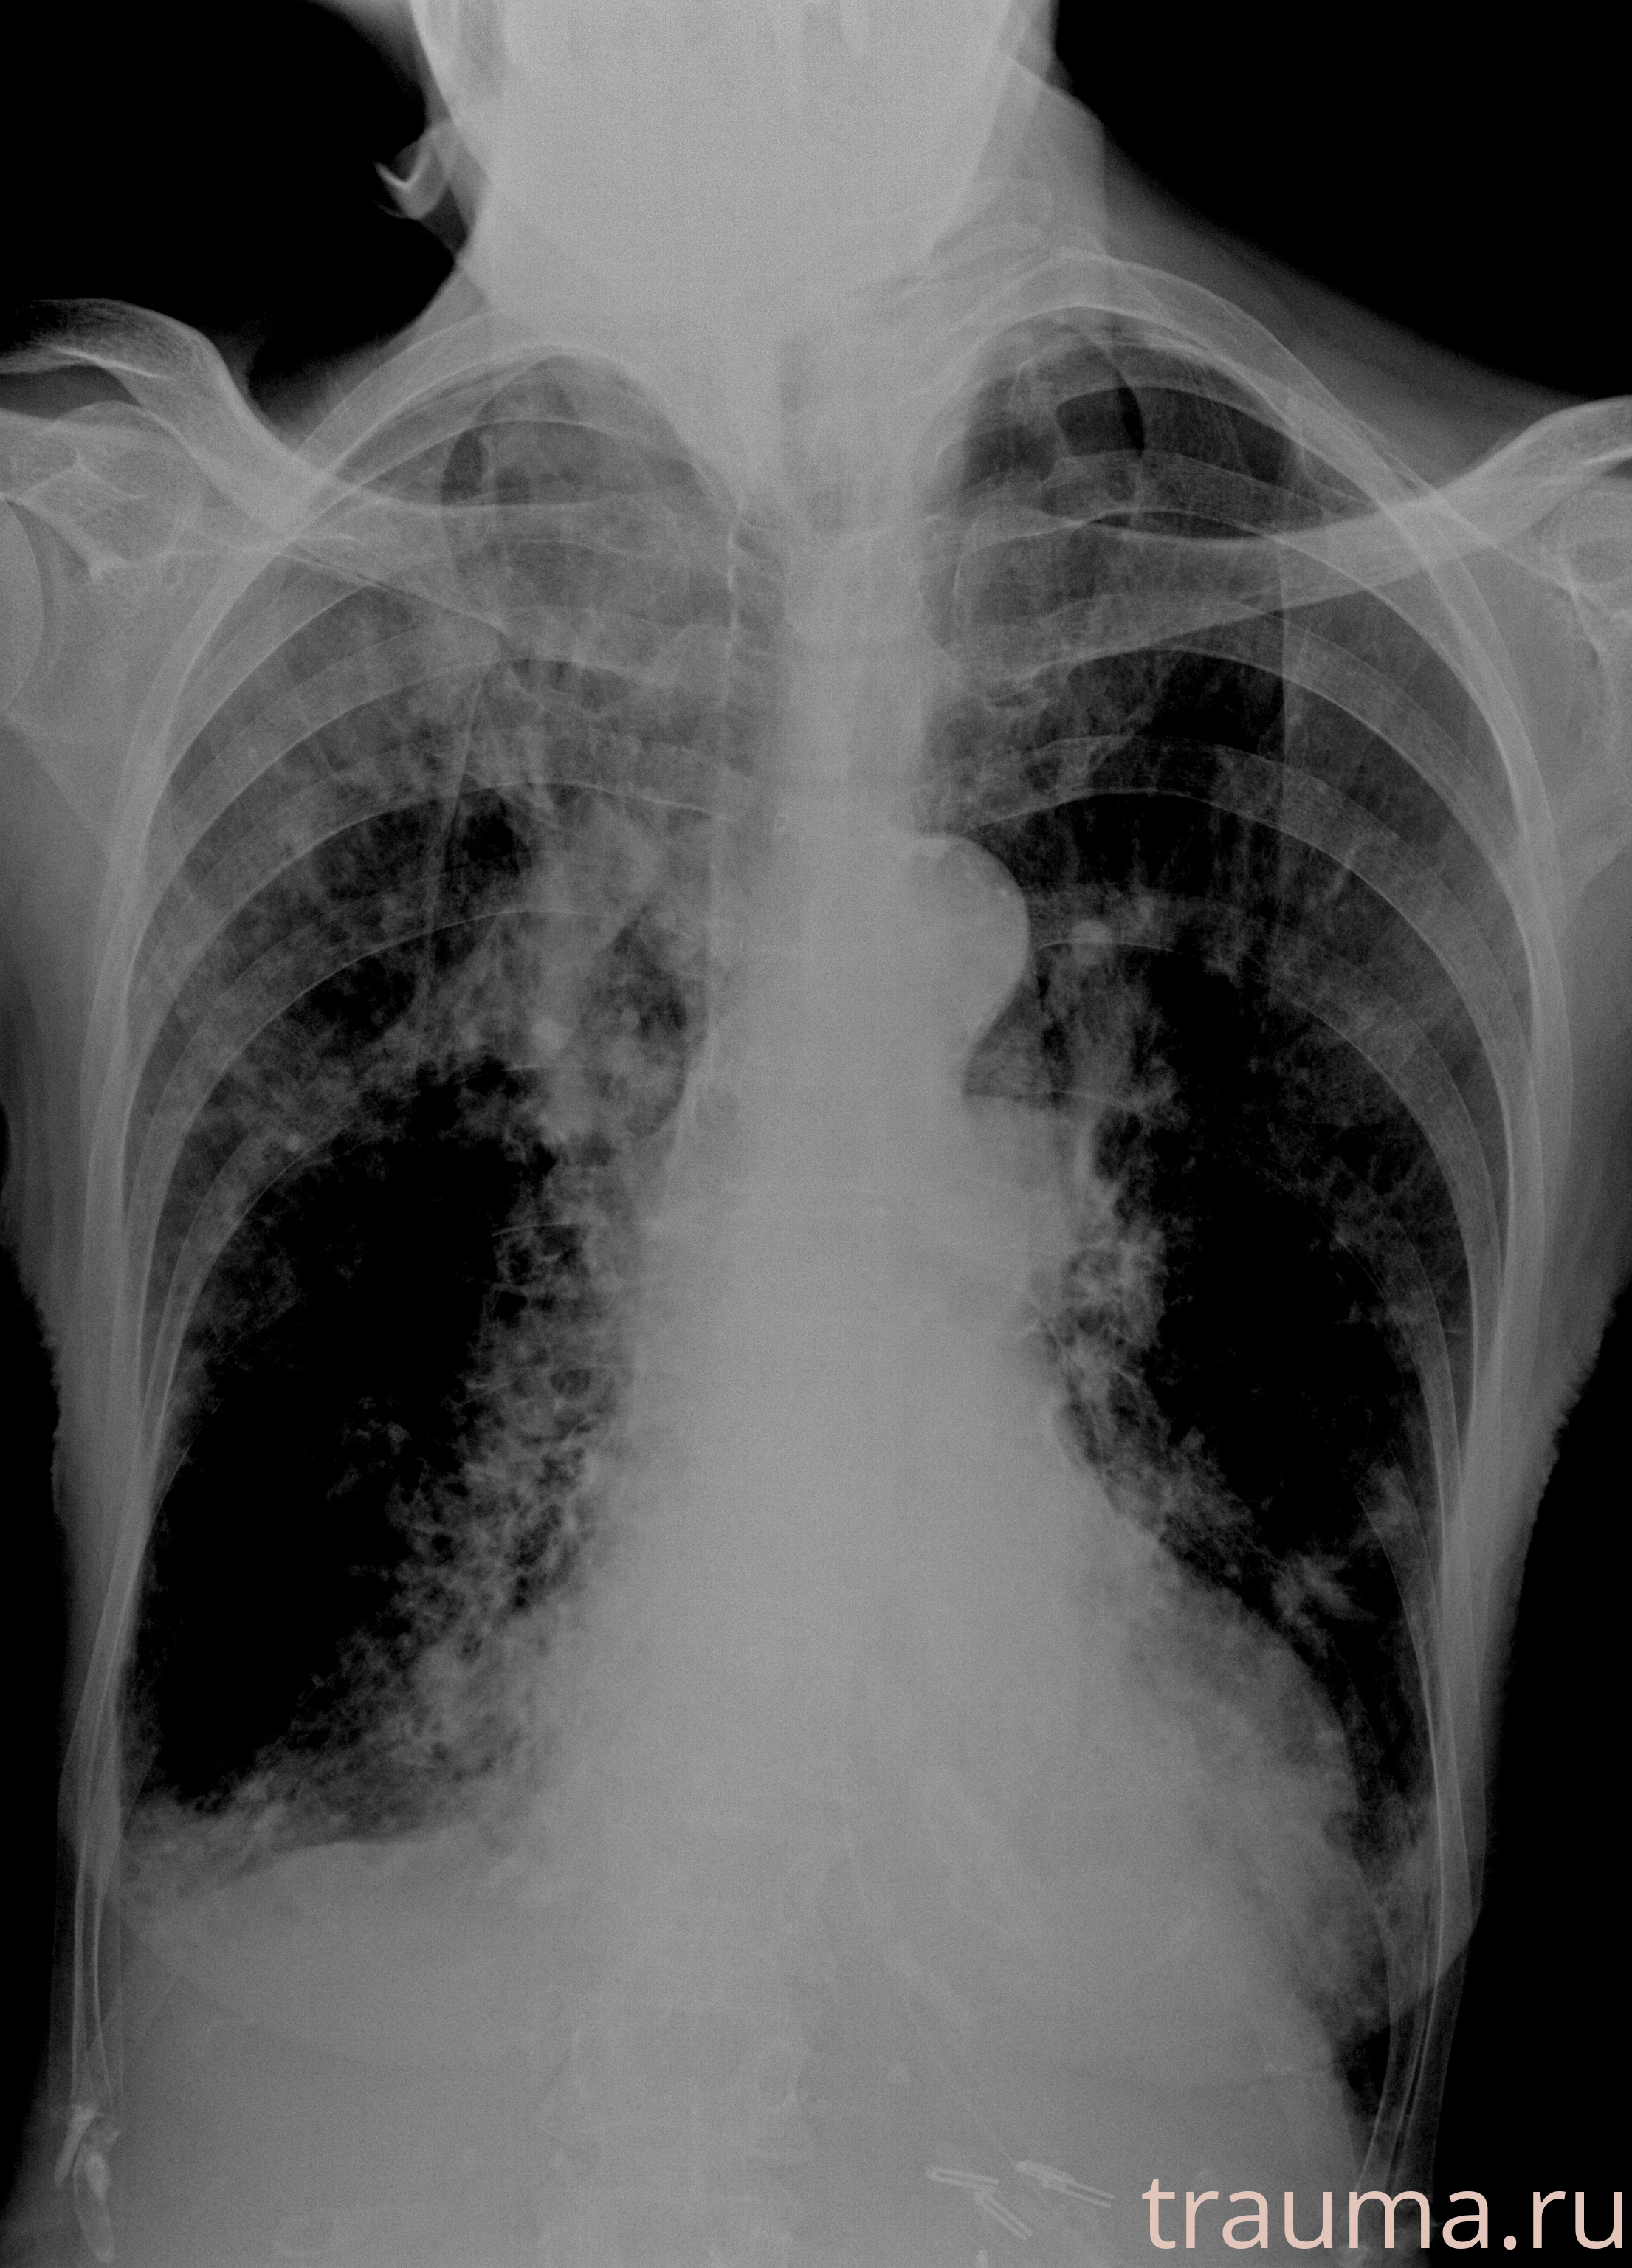

Рентген на дому: по вашему адресу приезжает врач-рентгенолог, травматолог-ортопед с мобильным рентгеновским аппаратом, проводит диагностику травмы или заболевания, делает необходимые рентгенограммы, дает рекомендации по дальнейшему лечению. Получить качественные снимки в домашних условиях возможно благодаря уникальной методике, разработанной МосРентген Центром для института  Склифосовского

при переломе шейки бедра и пневмонии от компании МосРентген Центр - партнера Института имени Склифосовского